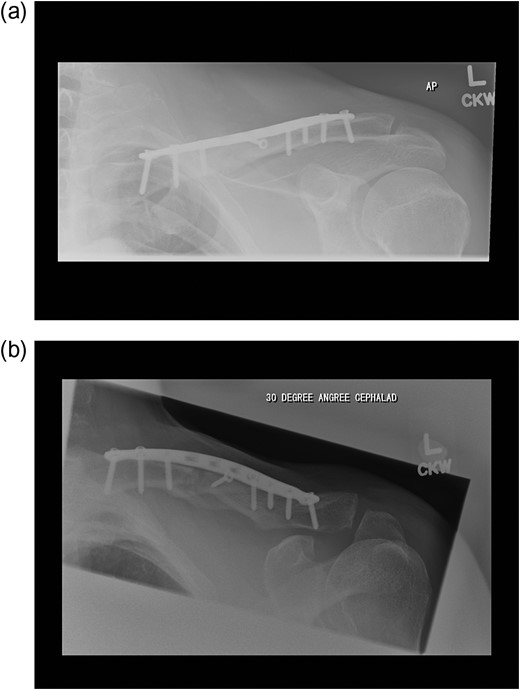

A 60-year-old gentleman presented with a displaced multifragmentary fracture of the left clavicle after a fall from a ladder. After discussion regarding the risks and benefits regarding operative versus non-operative treatment he elected for fixation (Fig. 1).

(a and b) Pre-operative radiographs of the fractured clavicle.